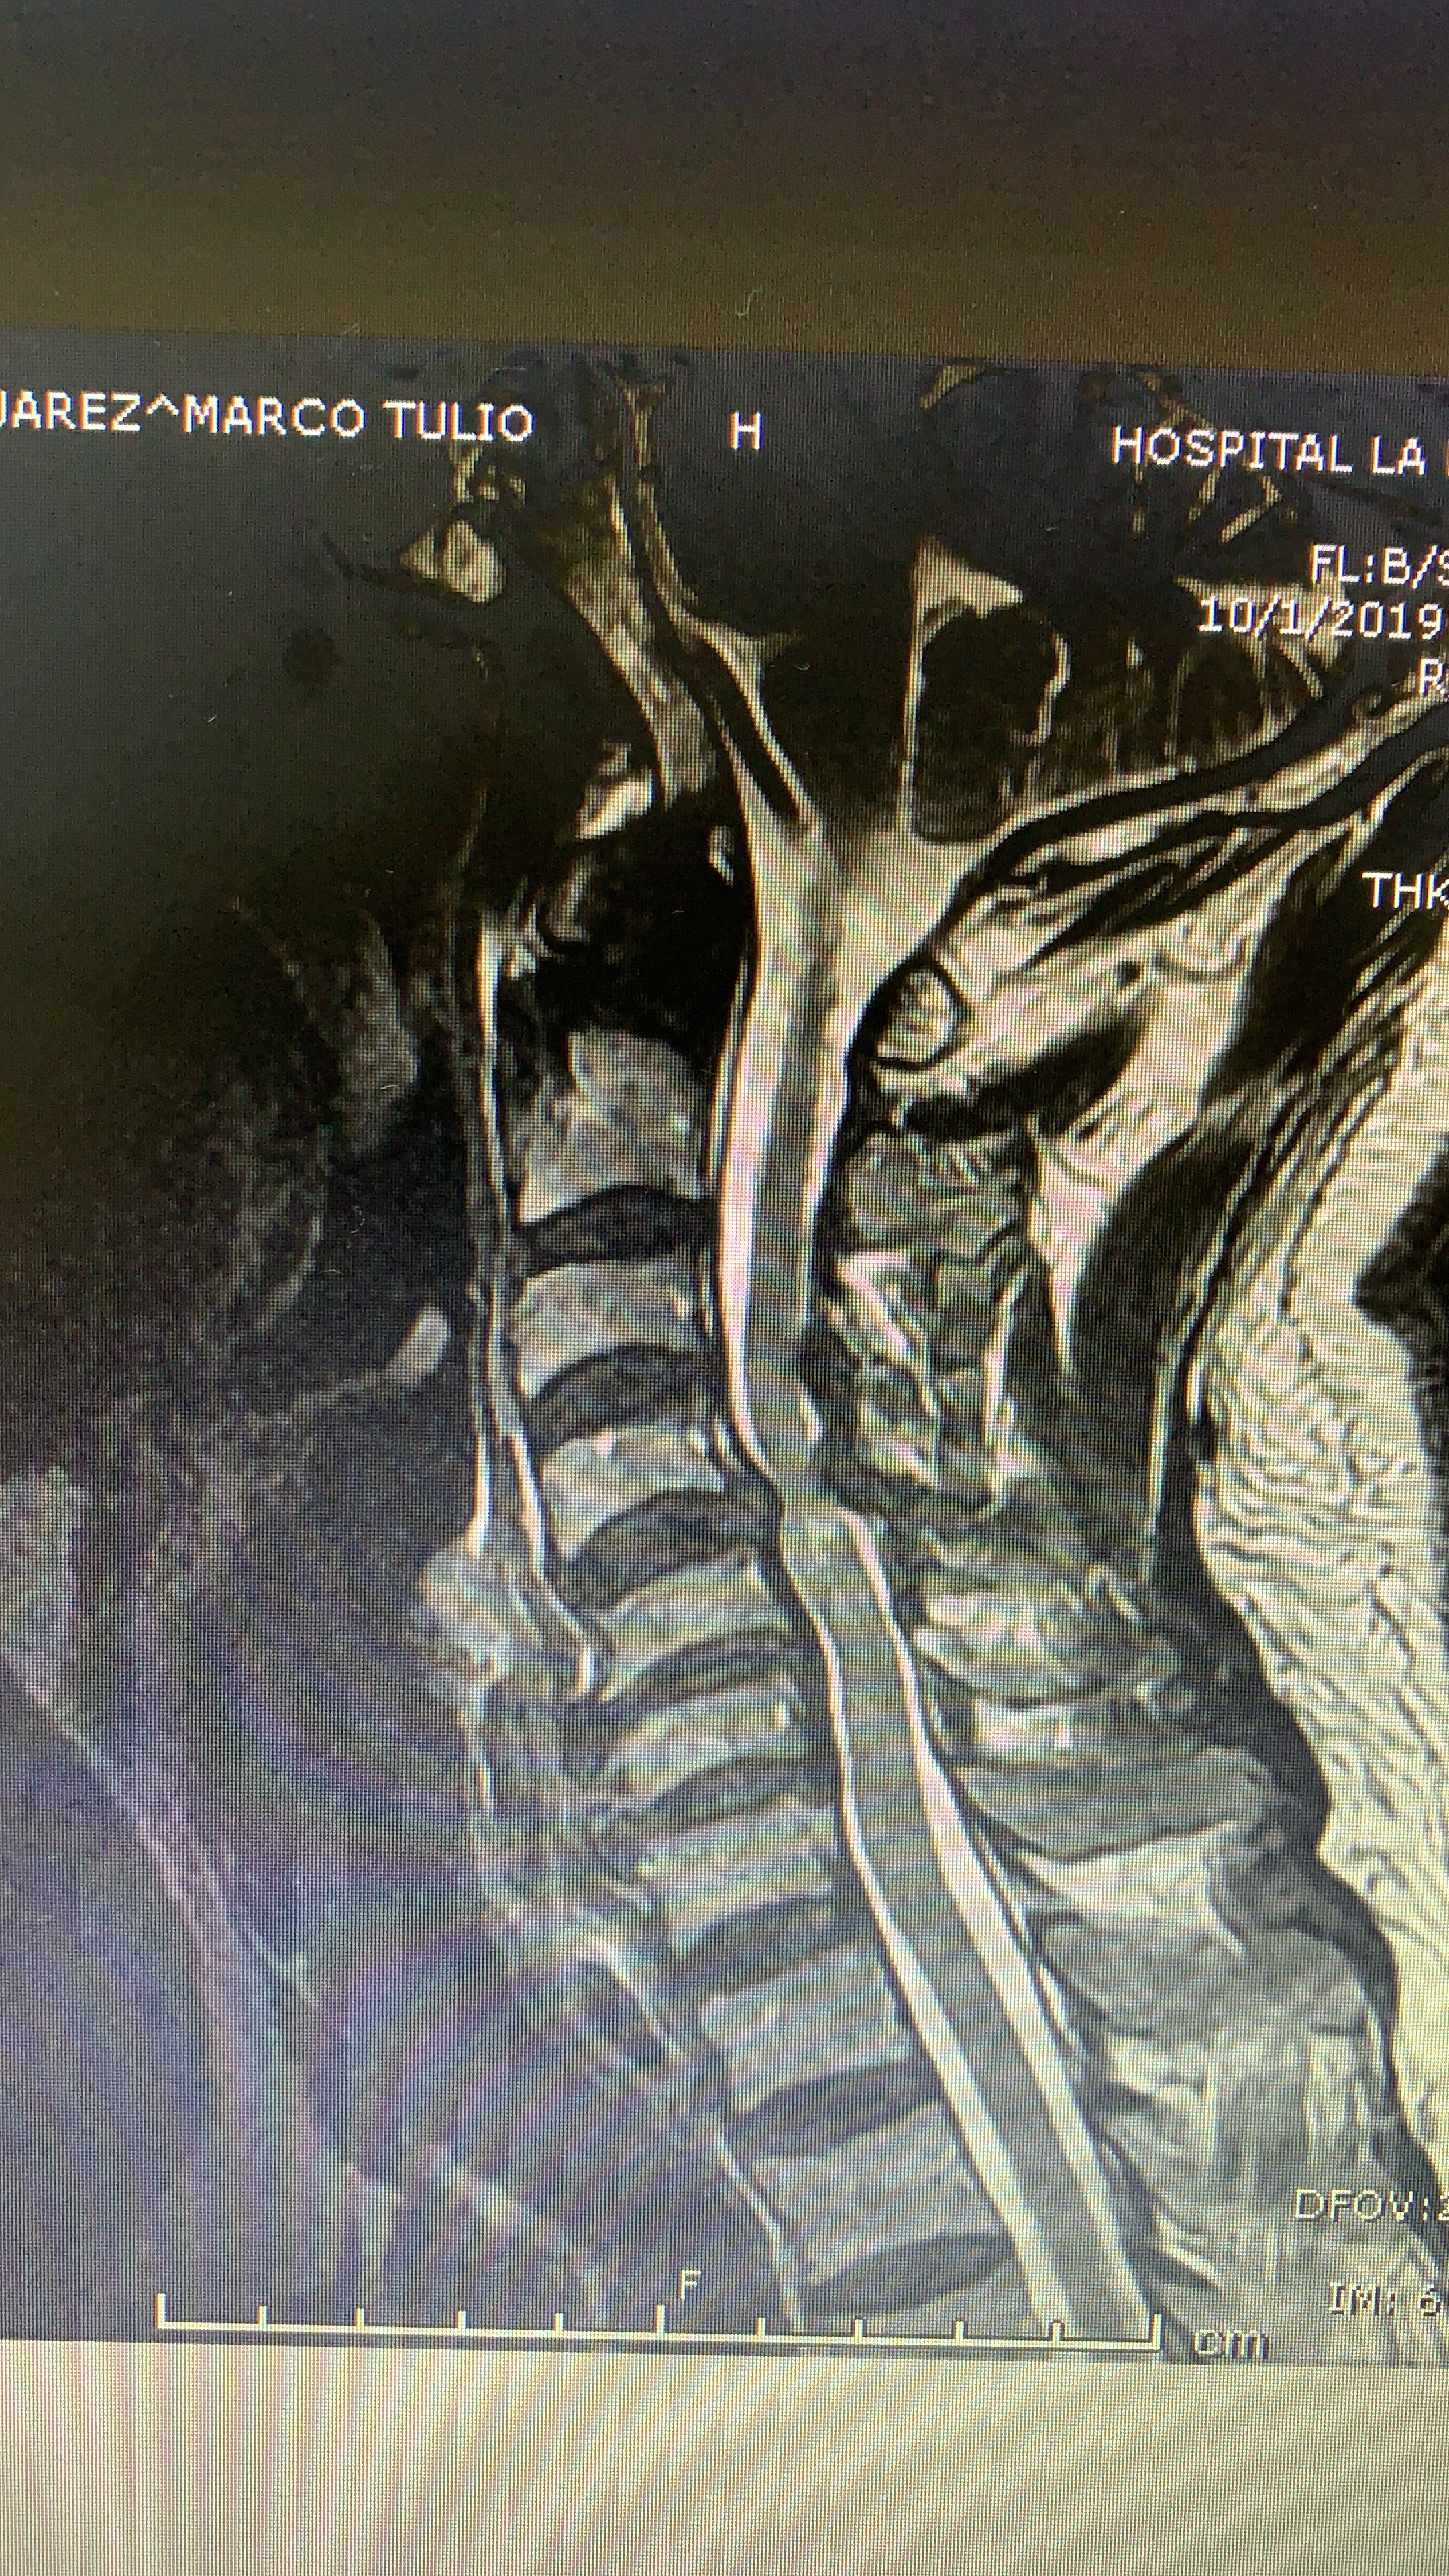

Galería de fotos clínica, servicios, cirugías, casos de pacientes Visítenos, ambiente limpio, agradable y seguro. Trabajando Operando en tiempos de coronavirus Dr Barquero Traumatologo Compartir en X (Se abre en una ventana nueva) X Comparte en Facebook (Se abre en una ventana nueva) Facebook Imprimir (Se abre en una ventana nueva) Imprimir Compartir en WhatsApp (Se abre en una ventana nueva) WhatsApp Enviar un enlace a un amigo por correo electrónico (Se abre en una ventana nueva) Correo electrónico Me gusta Cargando...